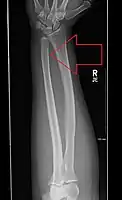

| Midshaft fracture of the radius and ulna | |

Front view of displaced fractured radius and ulna at wrist -

Side view of displaced fractured radius and ulna at wrist -